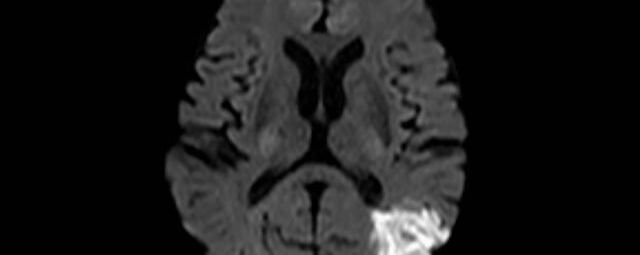

Kopf

• akute Schlaganfalldiagnostik und chronische Durchblutungsstörungen

• Diffusionswichtung

• Perfusionswichtung

• Suszeptibilitätswichtung

• MR-Spektroskopie

Diese Verfahren werden bei verschiedenen Fragestellungen in verschiedenen Körperregionen in die Messprotokolle sinnvoll eingefügt. Teilweise können dadurch Differenzierungenverschiedener krankhafter Prozesse verbessert werden.